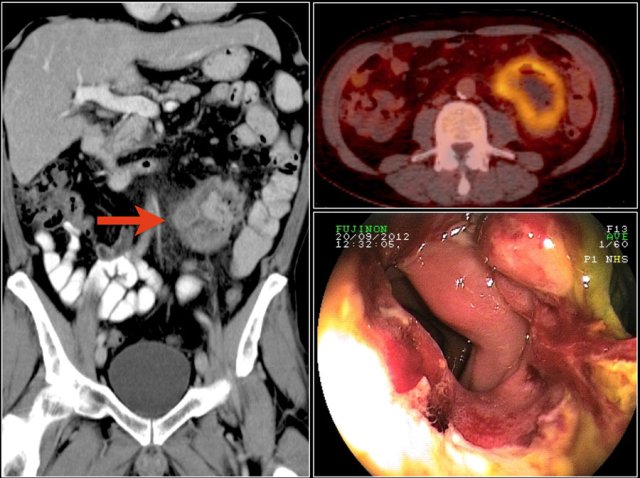

Here a typical lymphoma presenting as a large thick walled mass in the proximal jejunum with FDG uptake.

Dilated lumen at the site of the mass and prestenotic dilatation of the duodenum (red arrow)